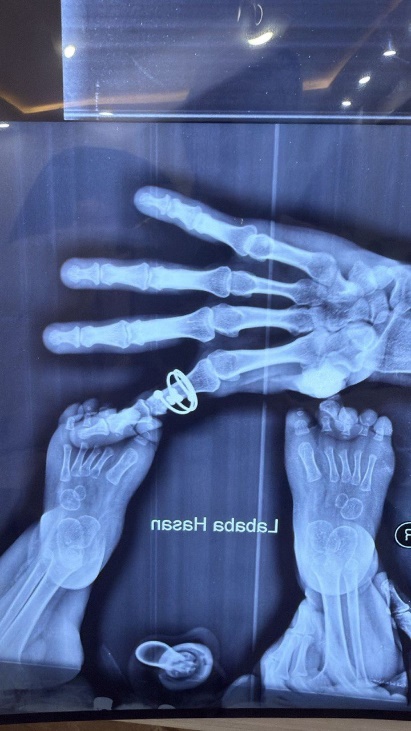

Figure 2: Hands and feet deformities

Short, broad hands and feet with clenched fingers and bilateral clubfoot, consistent with skeletal anomalies described in HPMR

Skeletal: Short broad hands/feet, clenched fists, bilateral clubfoot.

Figure 11: Skeletal deformities of the upper and lower limbs

Photographs showing short, broad hands with clenched fingers (upper image) and bilateral clubfoot deformities (lower image), consistent with skeletal abnormalities described in HPMRS.